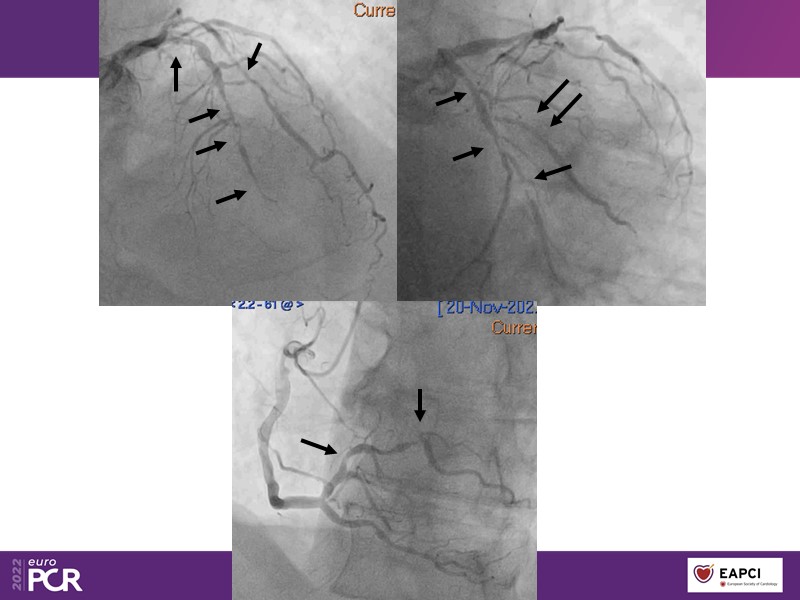

Alexandre Abizaid, Marco Valgimigli, Fazila Malik, Luca Testa, Patrick W. Serruys, Damiano Regazzoli, Kumar Prathap, and Sandeep Basavarajaiah take turns in this session to discuss two innovative technologies: a stent platform with nanotechnology and a novel drug-coated balloon (DCB). These novel technologies both have unique features that could change daily practice and improve outcomes.

- To understand how useful is a DES and DCB stent platform in complex coronary artery disease settings with case demonstrations and follow-up in diabetes mellitus